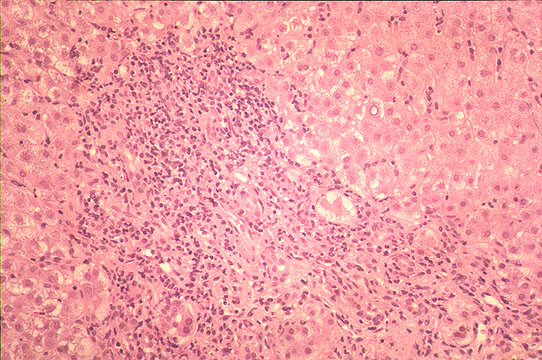

"Lobular disarray"

Fig 97 - "Lobular disarray": Loss of hepatocyte, inflammatory reaction, Kupffer cell mobilization an hepatocellular swelling distort the pattern of the liver plates somewhat confusing the lobular architecture.(H&E stain).

Fig 102 - Portal and periportal inflammation: Portal inflammation is always present in most portal tracts. The inflammatory cell s are mostly lymphocytes sometimes forming lymphoid follicles, plasma cell containing gamma globulins mostly IgG type, macrophages containing iron granules. There may be bile duct damage. Periportal inflammation with disruption of periportal limiting plate and piecemeal necrosis is also present. An acute hepatitis with portal inflammation and many segmented leucocyte and eosinophils is usually not viral. In this case of acute hepatitis B there is marked portal inflammation and periportal piecemeal necrosis with ballooned hepatocyte.